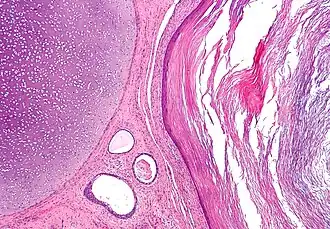

Description de cette image, également commentée ci-après

Micrographie d'un tératome montrant des tissus issus de trois couches germinales : mésoderme (immature cartilage - coin gauche supérieur de l'image), endoderme (glandes gastro-intestinales - Centre-bas de l'image) et ectoderme (épiderme - à droite sur l'image).

Coloration à l'hématoxyline et à l'éosine